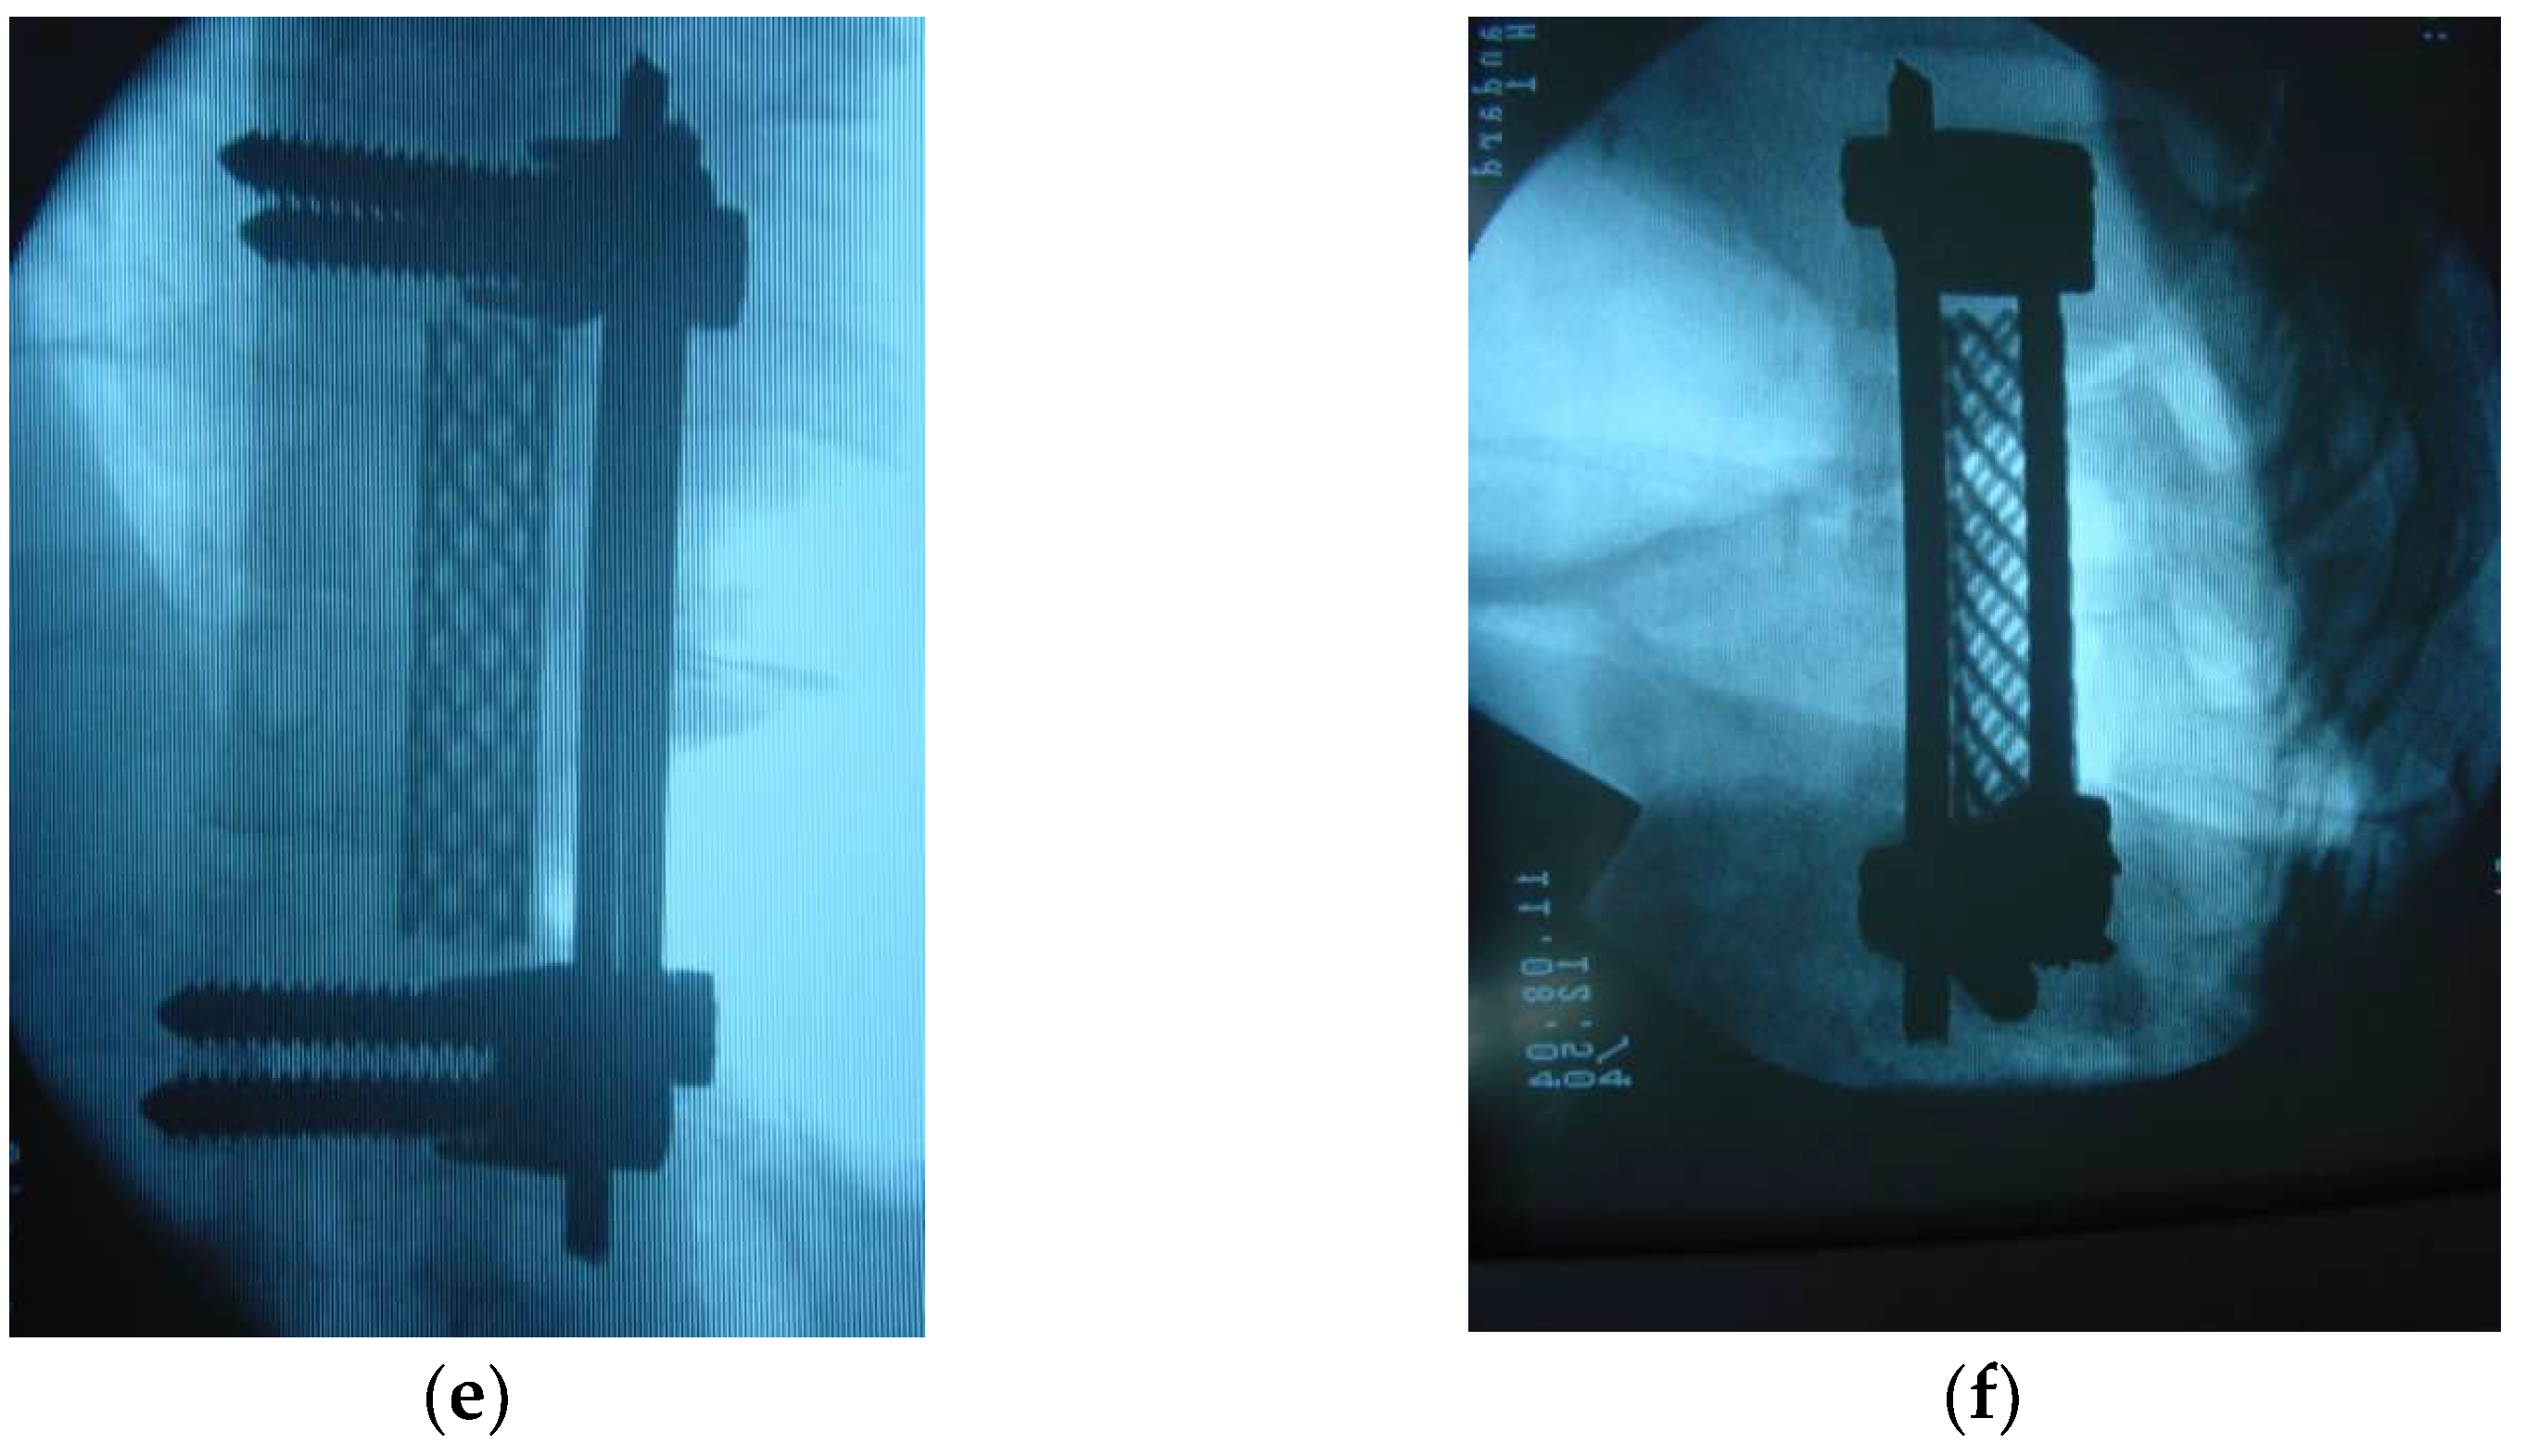

- Hee, H.T.; Majd, M.E.; Holt, R.T.; Pienkowski, D. Better treatment of vertebral osteomyelitis using posterior stabilization and titanium mesh cages. J. Spinal Disord. Tech. 2002, 15, 149–156. [Google Scholar] [CrossRef] [PubMed]

- Moon, M.S.; Woo, Y.K.; Lee, K.S.; Ha, K.Y.; Kim, S.S.; Sun, D.H. Posterior instrumentation and anterior interbody fusion for tuberculous kyphosis of dorsal and lumbar spines. Spine (Phila Pa 1976) 1995, 20, 1910–1916. [Google Scholar] [CrossRef] [PubMed]